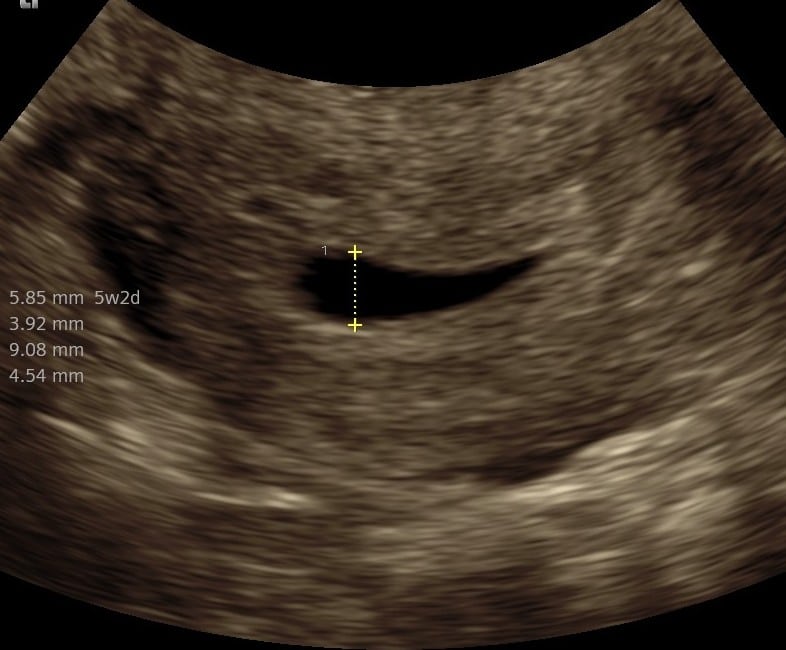

Praksisjordemoders tidlige tryghedsscanning (uger 5+0‑7+0) giver dig muligheden for:

- at bekræfte graviditet i livmoderen,

- at se hjerteblink, fra 6+3

- at få en foreløbig terminsberegning og stille spørgsmål til jordemoderen.